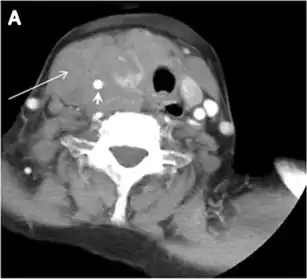

Fig. 4. A 45-year-old male patient presented with anterior mediastinal metastatic PTC lesions and occult primary on imaging. Histopathology examination of the resected thyroid gland revealed micro-foci of PTC; the largest, in the isthmus, measured 4 mm. a transverse greyscale ultrasound of the thyroid demonstrates homogeneous gland with normal echogenicity and size. No focal lesion or micro-calcifications. b Non-enhanced CT scan obtained as part of PET/CT examination shows a heterogeneous, large, relatively dense anterior mediastinal mass (white arrow) with peripheral calcification (arrowheads). Thyroid gland has normal CT appearance with no abnormal FDG uptake (not shown).[1]

Finally, the possibility of metastatic disease should be excluded. PTCs and medullary thyroid carcinomas tend to metastasize to regional lymph nodes. According to the AJCC/UICC TNM staging system, the nodal stage is classified by site: N1a indicates level VI nodal involvement, including paratracheal nodes; N1b indicates unilateral or bilateral lateral cervical nodal disease or superior mediastinal nodal disease (Figs. 4, 55 and and6)6).[1]